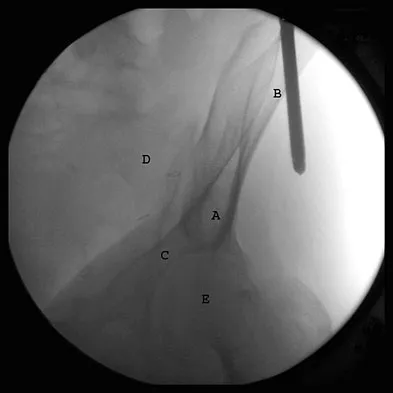

What letter in Figure 33 marks the correct starting point for a transiliac pelvic screw?